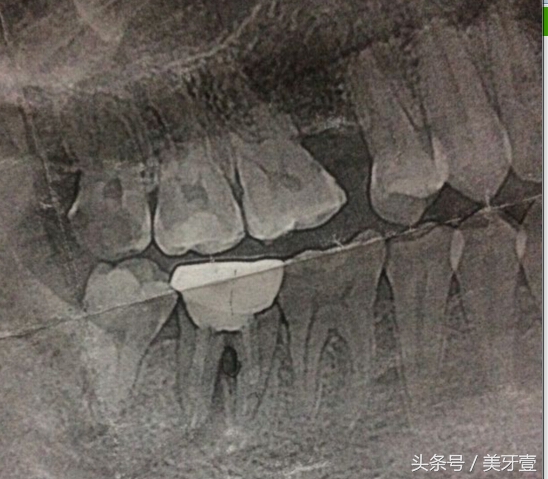

2、根折。根折按其部位可分为颈侧1/3、根中1/3和根尖1/3,最常见的是根尖1/3折。其折裂线与牙齿长轴垂直或有一定斜度,纵形根折很少见。因为牙根是埋在牙槽骨内的,所以需要拍X线片才能明确诊断,同时也有助于复查时的比较。根折多见于牙根完全形成的成人牙齿,原因是儿童的乳牙牙根发育未完全,根折在儿童身上多表现为牙齿的脱位。一般根折的位置越靠近牙根尖,预后就越好。

3、冠根折。冠根联合折断只占牙齿外伤的一小部分,但情况比较复杂,牙髓经常暴露,同样也需要X线片检查确诊,治疗方法相应的也比较复杂。